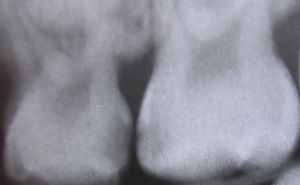

التشخيص

حدوث التسوس وتطوره

تقوم الحموض الناتجة من عملية تخمر السكاكر بحل العناصر المعدنية والعضوية التي تدخل في تركيب ميناء السن فتبدو المنطقة بيضاء طبشورية وذات ملمس خشن. ولدى تزايد إنتاج الحموض وعدم تطبيق الفلوريد الموضعي على الأسنان الذي يقوم عادة بإيقاف تطور التسوس، يتهدم الميناء وتصل الإصابة إلى العاج مشكلة حفرة التسوس التي يمكن ملاحظتها سريرياً ويبدأ الإحساس بالألم لدى التعرض إلى مؤثرات خارجية من سخونة وبرودة أو الضغط أثناء المضغ. عند إهمال معالجة التسوس في هذه المرحلة يزداد التخرب وتصل الإصابة إلى لب السن الذي يصاب بالالتهاب وترافقه موجات حادة من الألم وخاصة في أثناء الليل. إن عدم تطبيق المعالجة الملائمة في هذه المرحلة يؤدي إلى تموت اللب وإصابته بالتعفن وتتكون الخراجات الحادة والمزمنة والآفات الذروية التي تنتهي بقلع السن المصابة.